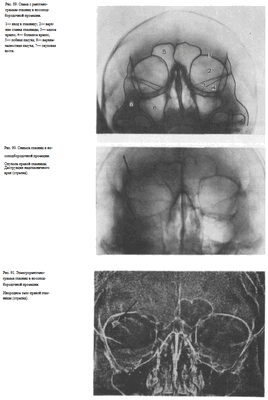

УКЛАДКИ СНИМОК ГЛАЗНИЦЫ В НОСОПОДБОРОДОЧНОЙ ПРОЕКЦИИ

Назначение снимка. Изучение состояния костей, образующих вход в глазницу, костной структуры верхней и наружной ее стенок.

Укладка больного для выполнения снимка сходна с укладкой для выполнения обзорного снимка в этой же проекции. В данном случае используюткассету размером 13X18 см, располагая ее в кассетодержателе в поперечном положении. Больной прилежит к столу подбородком и кончиком носа,переносье соответствует центру кассеты. Центральный пучок излучениянаправляют на центр кассеты. Фокусное расстояние—100 см.

В этой же укладке может быть выполнен снимок одной (правой или левой) глазницы. В таких случаях центр снимаемой глазницы соответствует центру кассеты, и на него отвесно направляют пучок излучения, используя тубус или диафрагмирование пучка излучения с помощью щелевой диафрагмы. Фокусное расстояние—100 см (рис. 88).

Информативность снимка. На снимке хорошо видны вход в глазницу, структура ее стенок, иногда малое и большое крыло клиновидной кости (рис. 89). На снимке в этой проекции могут быть выявлены деструктивные изменения стенок глазницы и инородные тела в ее полости (рис. 90, 91). Для выявления изменений в области верхней стенки глазницы (например, при

диагностике переломов) снимок целесообразно выполнять не в носоподбородочной, а в подбородочной проекции.

Укладка больного для выполнения снимка, информативность снимка, критерии правильности технических условий съемки и правильности укладки те же, что для снимка крыльев клиновидной кости и верхних глазничных щелей.

В качестве примера информативности снимка глазниц в носолобной проекции для выявления инородных тел глаза и деструктивных изменений стенок приводим два наблюдения.

Одно из них — случай ранения глаза металлической стружкой (рис. 93), другое — случай деструкции верхненаружного края глазницы при доброкачественной опухоли слезной железы (рис. 94).